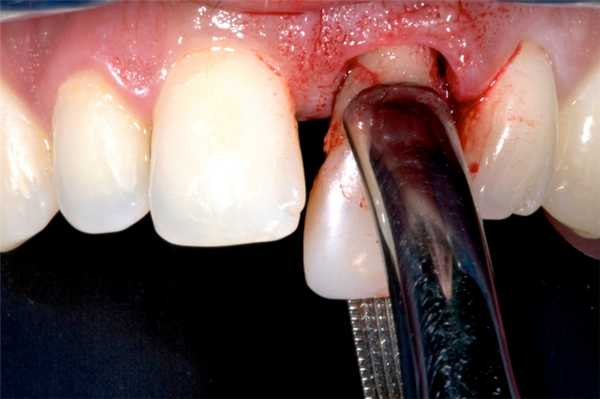

Прободение (перфорация) дна верхнечелюстной пазухи может произойти во время удаления верхних больших, реже - малых коренных зубов. Этому способствуют анатомические особенности взаимоотношения между корнями этих зубов и дном верхнечелюстной пазухи. При пневматическом типе строения пазухи верхушки корней больших и малых коренных зубов отделены от ее дна тонкой костной перемычкой. В области первого и второго больших коренных зубов толщина ее бывает 0,2-1 мм. Иногда верхушки корней этих зубов вдаются в пазуху и выступают над ее дном.

Рис. 64 Удаление верхнего моляра со вскрытием верхнечелюстной пазухи

Перфорация дна верхнечелюстной пазухи может произойти и по вине врача. Это бывает при травматичном удалении зуба щипцами или элеватором, разъединении корней в области бифуркации долотом, а также во время обследования лунки хирургической ложкой, когда ее грубо продвигают вверх, пытаясь с усилием удалить грануляционную ткань со дна лунки